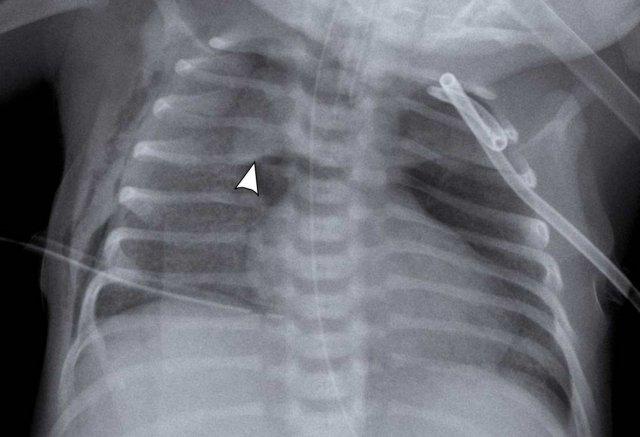

Trẻ sinh non, 28 tuần tuổi thai được điều trị vì hội chứng suy hô hấp (RDS).

Máu qua ống nội khí quản.

Image

- Patchy

opacifications in the right lung, due to hemorrhage. - Xẹp phổi

thùy dưới phổi trái (mũi tên) với tình trạng căng phồng nhẹ thùy trên phổi trái. - Good position

of ETT. - Low position of umbilical vein line, NG tube in situ.